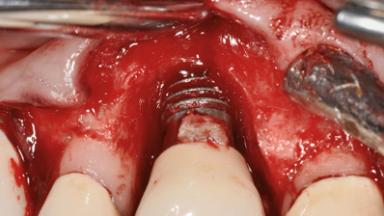

Peri-implantitis Treated by an Antimicrobial and Regenerative Approach

A 73-year-old woman was referred to the Division of Periodontology (University of Geneva School of Dental Medicine) after repeated unsuccessful treatment of a peri-implant infection. She was systemically healthy and did not smoke. The patient’s history revealed that, three years earlier, an immediate implant (Straumann Tapered Effect RN 4.8/4.1; Institut Straumann AG, Basel, Switzerland) had been inserted to replace the upper right central incisor. A metal-ceramic crown had been delivered using an adhesive resin cement. One year later, the patient had consulted another dentist due to discomfort in the soft tissues in the implant region. There was a suppurating peri-implant pocket, 10 mm deep. Peri-implant bone loss and excess luting cement were seen on the radiograph. The situation was treated with non-surgical debridement, amoxicillin, and repeated submucosal irrigation with a chlorhexidine digluconate solution. The patient was referred after the suppuration had persisted for several months.